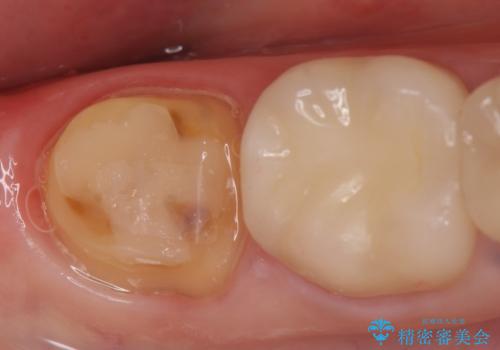

- 右下の奥歯でものを咬むと違和感があるので診て欲しいといらっしゃった方の症例です。

右下6は神経が死んでいたため根管治療を行い、オールセラミッククラウンによる補綴を行いました。

右下7は冷たいものがしみていたため、銀歯を除去後、オールセラミッククラウンによる補綴を行いました。